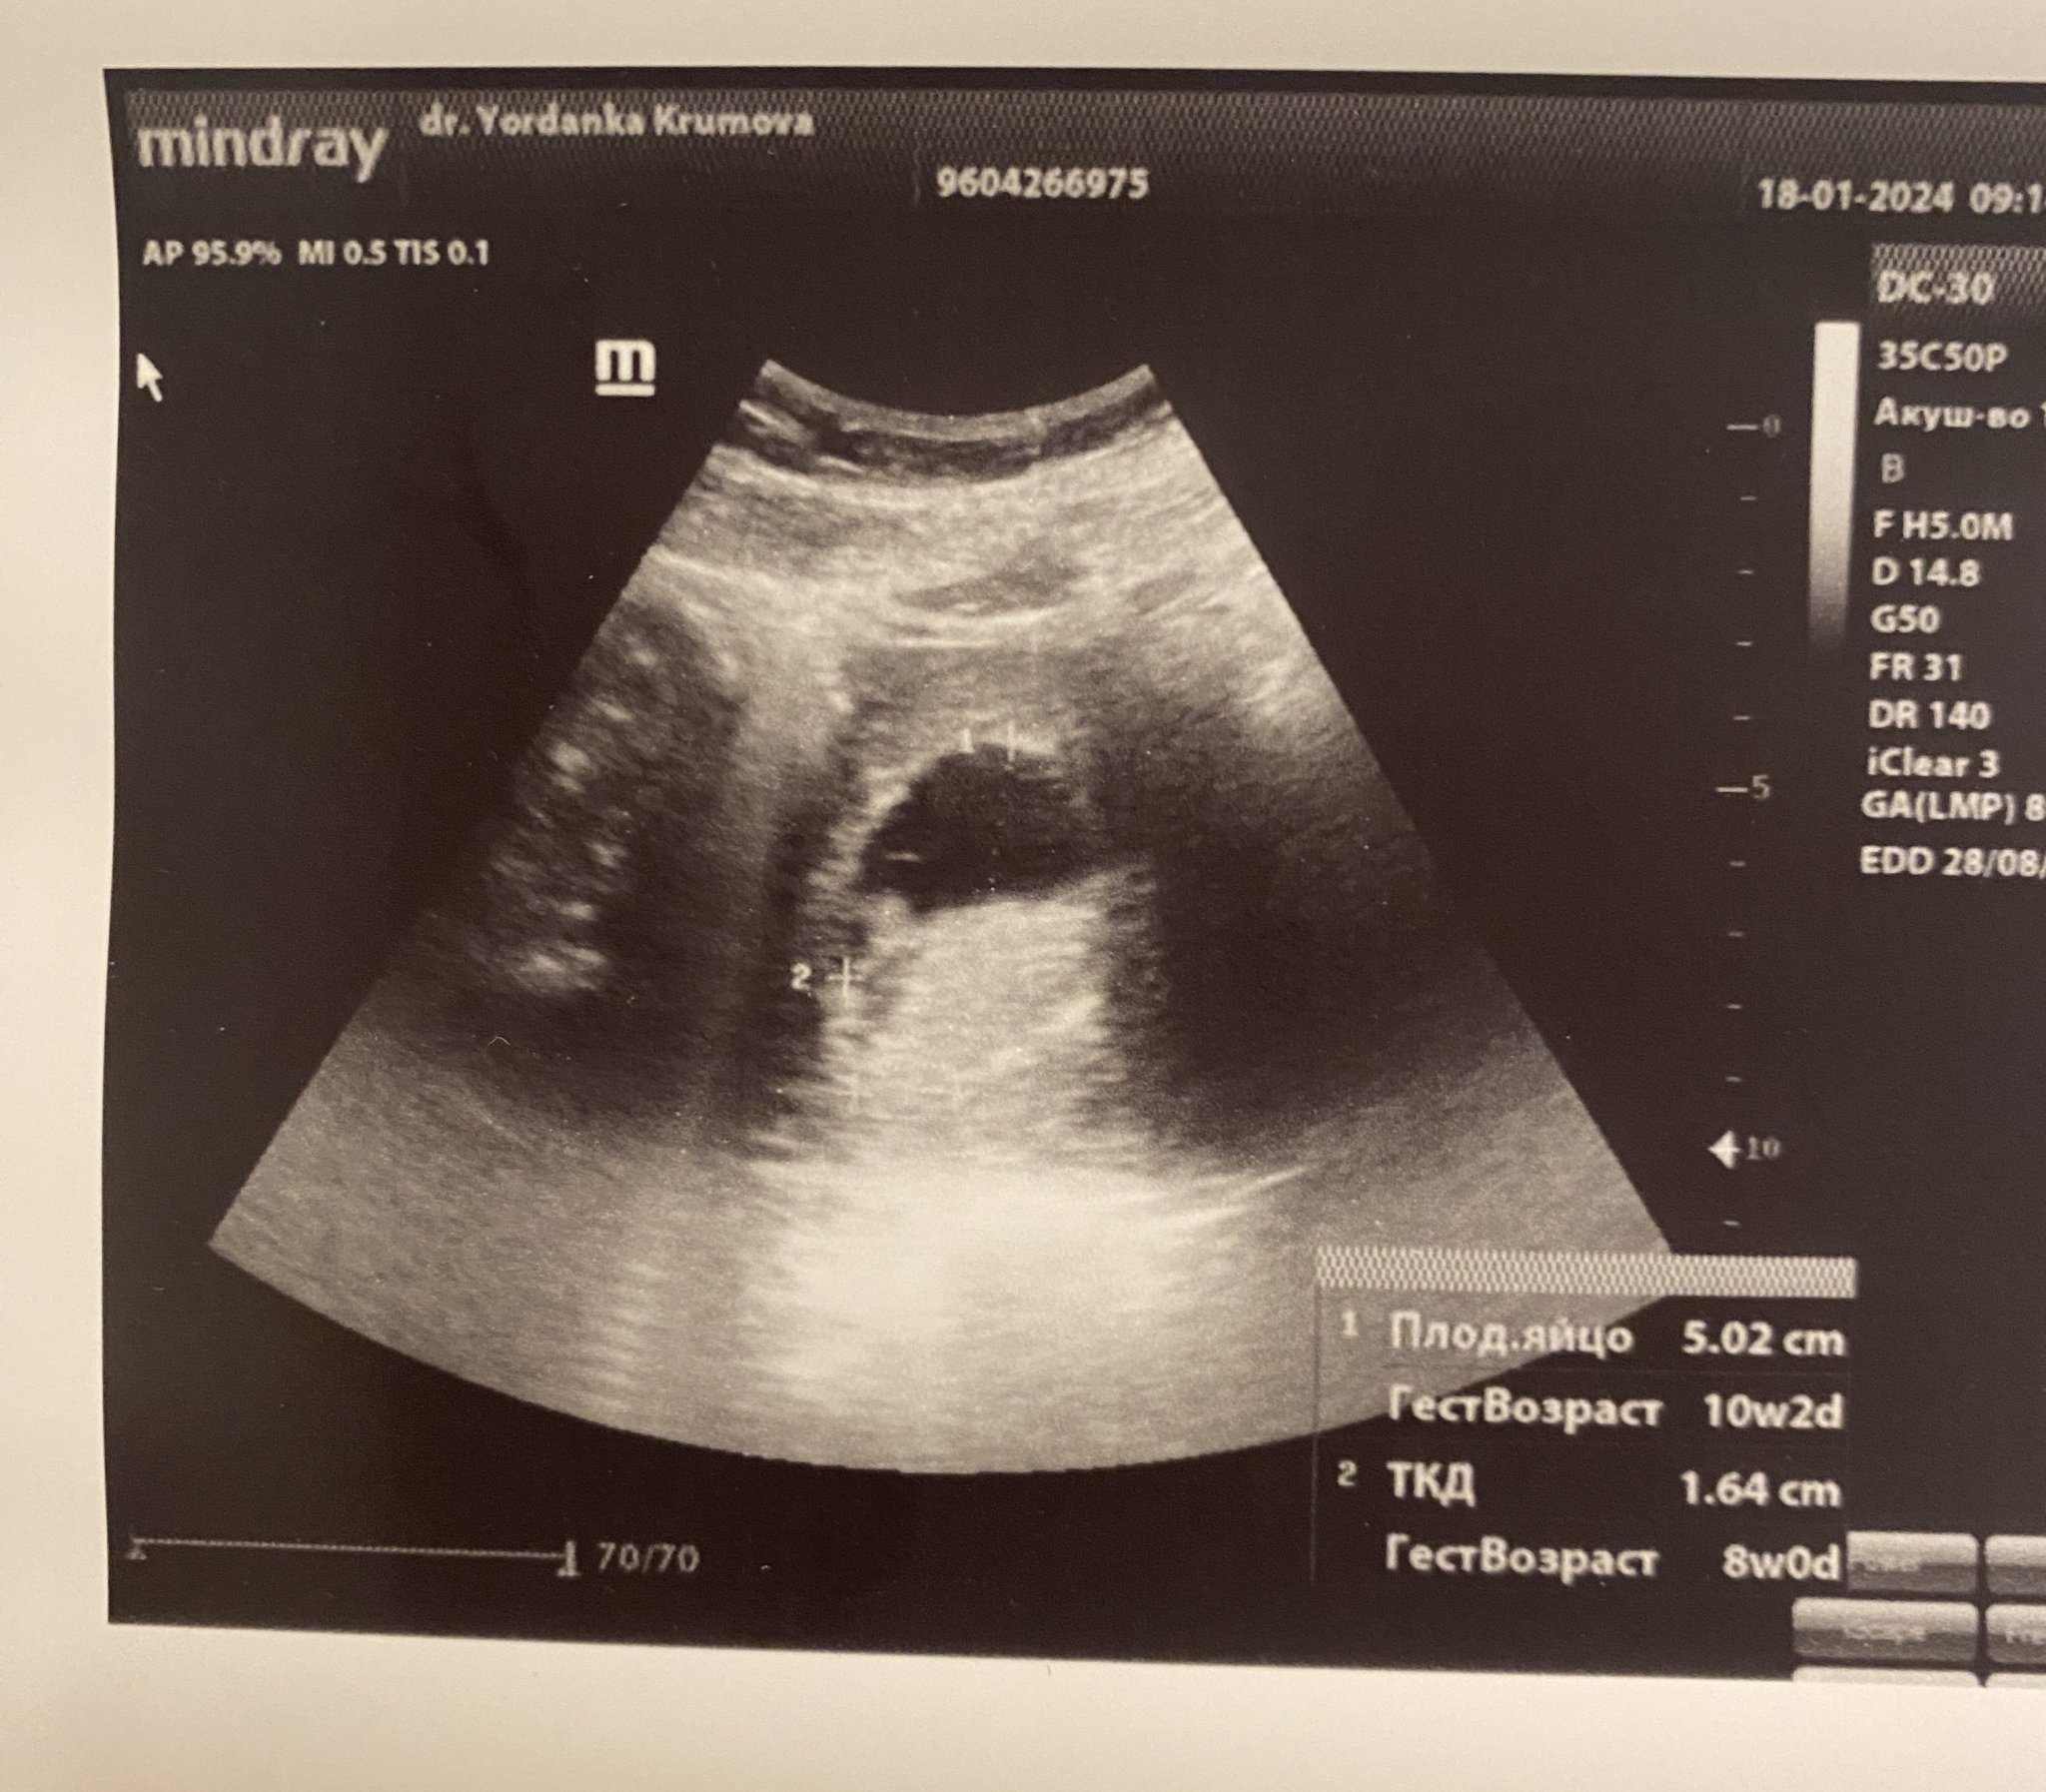

Здравейте, момичета Blush Бременна съм за първи път, на 27 години, в 8ма г.с съм с термин 28.08.24. Вчера бях на преглед за 3ти път, АГ каза, че всичко е наред, следващия ми преглед е на 16ти февруари. Прегледа беше през корема, а не вагинално, извинявам се, но не съм сигурна относно термините Sweat Smile Дадоха ми снимка от ултразвука, но аз абсолютно нищо не различавам на снимката и съм се притеснила, че не се вижда плода и дали всичко е наред наистина Sad Някой мнения относно снимката? Все още всичко ми е толкова ново и непознато

Здравей и добре дошла. По принцип ти е малко раничко още за коремен, но щом така е преценил докторът. Това, което се вижда като лъч светлина са ми казвали, че е черво, което допълнително затруднява образа от коремния ехограф. На мен ми се струва, че горе вдясно виждам бебето, а долу вляво жълтъчното мехурче, но са по скоро като сянка. Тази снимка, която имаш сякаш измерва гестационния сак.  Същевременно виж от къде да къде го е хванала, втората точка е извън гестационния сак и и затова долу ти пише, че по сак е 10+2 г.с., което според мен е неточно, защото е неправилно хванато при измерването. Сърдечни пулсации видя ли вече?

Много благодаря за отговора! Не, не съм видяла още сърдечни пулсации. Чудя се дали да не отида на преглед и при друг доктор…